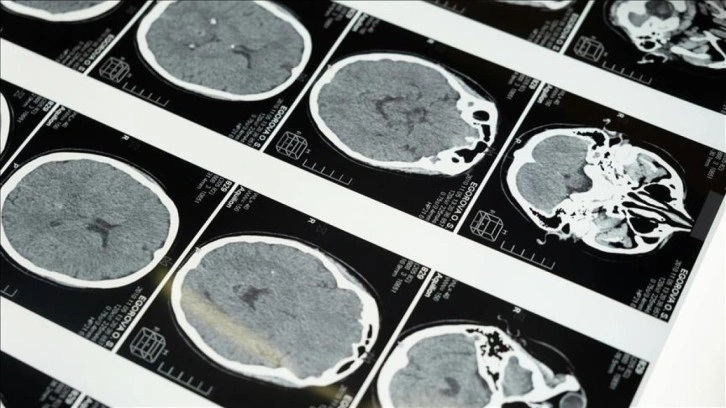

İstanbul'da düzenlenen 1. Dünya Girişimsel Nöroloji ve Nöroşirürji Kongresi'nin (WINNC 2025) düzenleme komitesinde yer alan Eskişehir Osmangazi Üniversitesi Tıp Fakültesi Nöroloji Ana Bilim Dalı Öğretim Üyesi ve İnme Merkezi Sorumlusu Prof. Dr. Atilla Özcan Özdemir, inmenin beyin damarlarının tıkanması (iskemik) ve beyin kanaması şeklinde gelişen iki türünün olduğunu söyledi.

İskemik inmenin dünyada ve Türkiye’de sık görüldüğünü, özellikle kadınlarda görülme sıklığının arttığını ve meme kanserinden daha yaygın hale geldiğini belirten Özdemir, inmenin başlıca ölüm nedenlerinden biri olduğunu ve erişkin yaşta kazanılmış engelliliğin en sık nedeni olması nedeniyle ciddi bir halk sağlığı sorunu haline geldiğini kaydetti.

"Özellikle pıhtıyla tıkanan beyin damarının açılmasıyla ilgili stratejiler gelişti. İnmede erken dönemde yapılan damar açma tedavileri konusunda ülke olarak iyi durumdayız. İnme tedavisinde pıhtıyla tıkalı beyin damarının anjiyo yoluyla açılması mümkün. Böylelikle hastanın 3 ay sonra, 1 yıl sonra kendi işini yapabilecek hale getirilmesi sağlanabiliyor. İnme merkezlerinde uygulanabilen bu işlemi ilk 24 saat içerisinde belirli hasta gruplarına yapabiliyoruz. İlk 24 saat çok kritik, bu müdahaleler de sadece inme merkezlerinde yapılabiliyor."